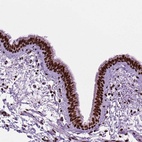

Immunohistochemical staining of human bronchus shows strong nuclear positivity in respiratory epithelial cells.